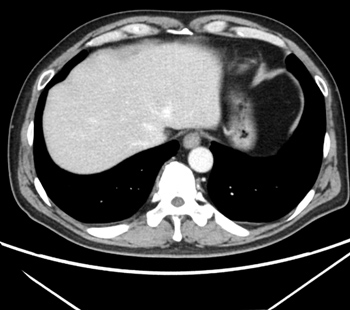

2023.2.2 복부 CT

2025.3.14 복부 CT

※ 동일한 조건에서 촬영된(사진에 대한 별도 조작이 처리되지 않은) 본원에서 진료 및 치료를 받으신 고객(들)의 사진입니다.

사진의 결과는 사례에 기반한 참고 자료로, 개인별 치료 결과는 상이할 수 있습니다.

또한 치료 후에는 홍반, 열감, 피로감, 근육통, 저혈습 등 부작용이 발생할 수 있습니다.